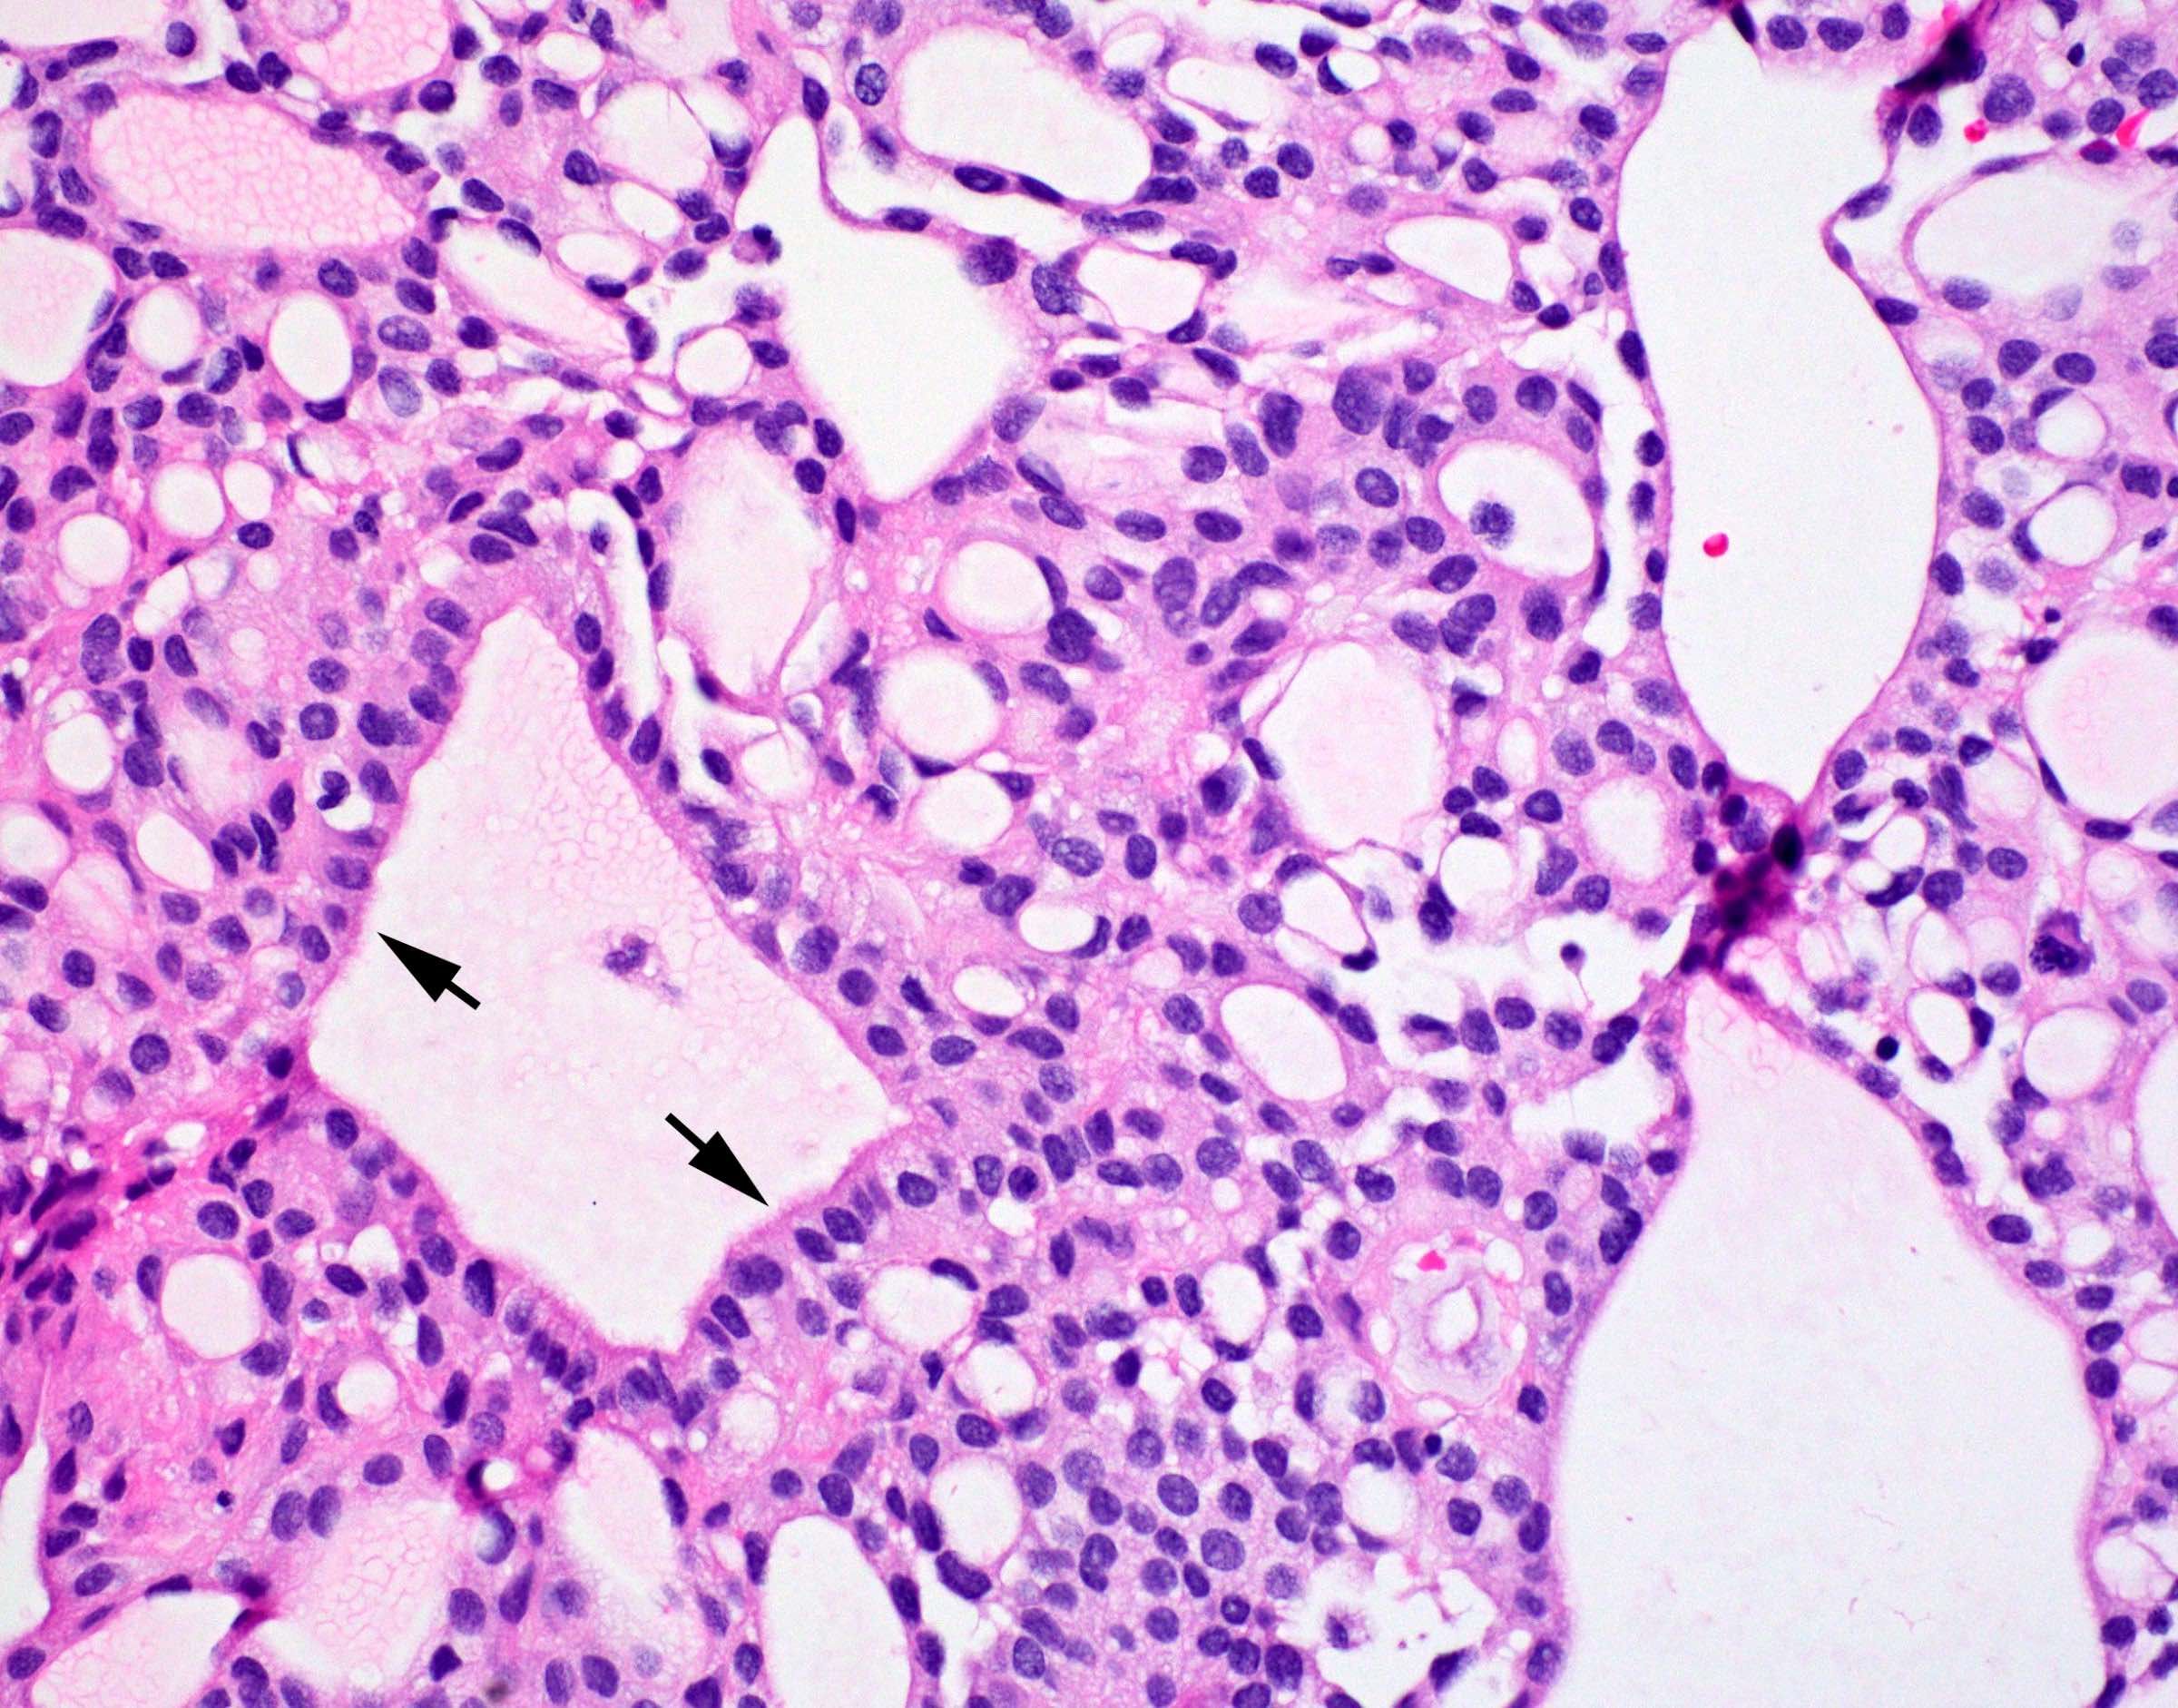

Microscopic (histologic) description

- Perivascular pseudorosettes, true ependymal rosettes, lumina and fibrillar areas

- Can have nonpalisading necrosis, areas of cystic or myxoid degeneration, calcifications, degenerative atypia, neuronal differentiation and rarely metaplastic elements

- Morphologic subtypes have no clinicopathological significance and include papillary, clear cell and tanycytic

Microscopic (histologic) images